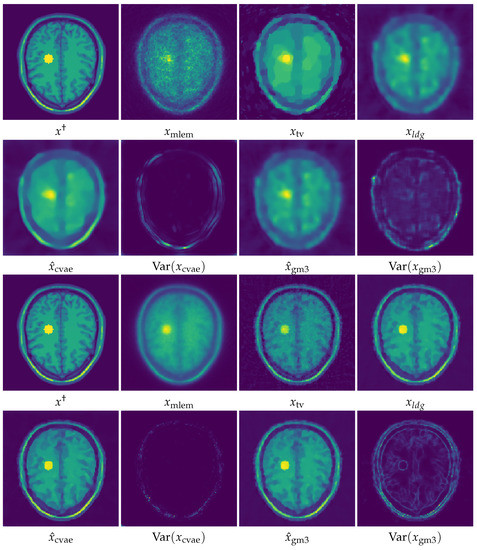

5. Numerical Experiments and Discussions